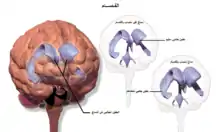

_-_ara.png.webp)

يرتبط الفصام باختلافات دقيقة في بُنيان الدماغ، وُجدت لدى 40 إلى 50% من الحالات، وفي كيمياء الدماغ أثناء الحالات الذهانية الحادة.[10] وقد أظهرت الدراسات التي تستخدم الاختبارات العصبية والتصوير العصبي مثل التصوير بالرنين المغناطيسي الوظيفي والتصوير المقطعي بالإصدار البوزيتروني لفحص الاختلافات الوظيفية في نشاط الدماغ بأن هذه الاختلافات تحدث غالبًا في الفص الجبهي وقرن آمون والفص الصدغي.[68] وقد تم الإبلاغ عن وجود انكماشات في حجم الدماغ أصغر من تلك التي وُجِدت في مرض الزهايمر في مناطق من القشرة الأمامية والفصوص الخلفية. ومن غير المؤكد ما إذا كانت تلك التغييرات في الحجم آخذه في التقدم أم أنها كانت مسبقة الوجود قبل بداية المرض.[31] وقد تم ربط تلك الاختلافات بعجز الإدراك العصبي والذي غالباً ما يرتبط بالفصام.[69] نظرا لتغير الدارات العصبية، فقد اقتُرح أن يُنظر إلى الفصام وكأنه مجموعة من اضطرابات التطور العصبي.[70] هناك بعض النقاشات حول إذا ما كان العلاج بمضادات الذهان ذاته يسبب انكماشات في حجم الدماغ.[71]